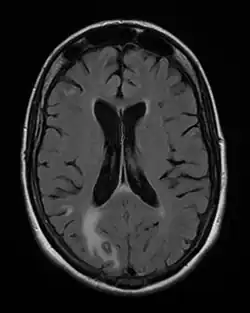

Toxoplasmose cerebral com envolvimento primário no lobo occipital direito. Mulher de 48 anos com AIDS.

O diagnóstico é pela sorologia, ou seja, detecção dos anticorpos específicos contra o parasita, como as imunoglobulinas IgM, que só existem nas fases agudas, e IgG que está aumentada na fase crônica da doença.